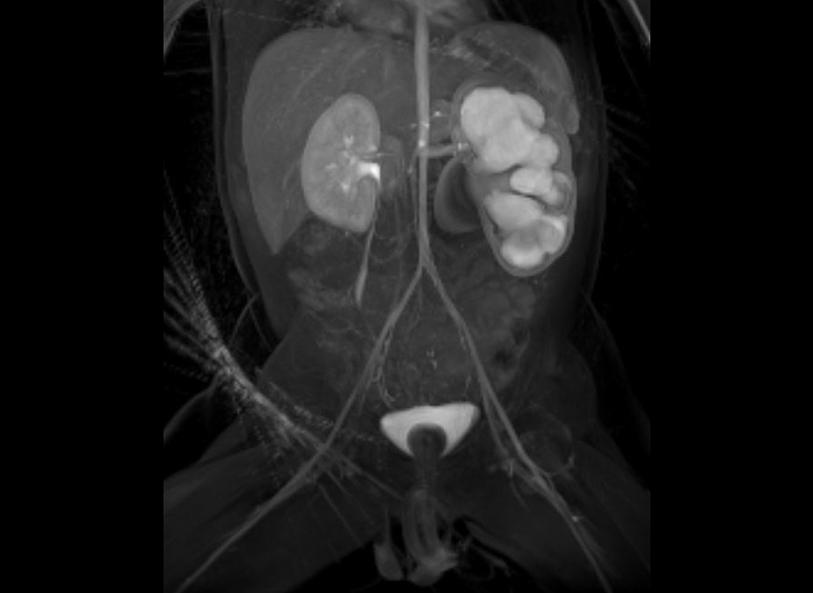

Video urodynamic studies (UDS) are a routine part of care for children born with spina bifida to study bladder function. Traditionally, these studies have relied on fluoroscopy, which requires X-ray imaging. A new technique, pioneered at UVA Health Children’s, uses contrast-enhanced voiding ultrasound (ceVUS) instead. And clinical trials show many benefits.

Diagnostic-wise, the contrast ultrasound appears as effective as X-ray imaging but avoids radiation. An added benefit is positive reactions from parents. They appreciate the lack of radiation exposure and the comfort aspects as well.

In 2020, Kern and the UVA Health Children’s pediatric urology and radiology team started actively trialing the ceVUS modality in conjunction with UDS, which uses an FDA-approved contrast material. In their study, they found that they were able to diagnose pathologies just as effectively with the ultrasound imaging compared to X-ray imaging.

“The imaging quality is quite comparable with the added benefit of continuous imaging, whereas you can’t continuously image an entire UDS study with X-ray due to the radiation,” Kern says.

Overall, ceVUS allows for real-time and continuous diagnostics. If any anatomical changes occur during the study, the ceVUS can actively capture that moment. And, for families, the study offers a better experience with less anxiety.